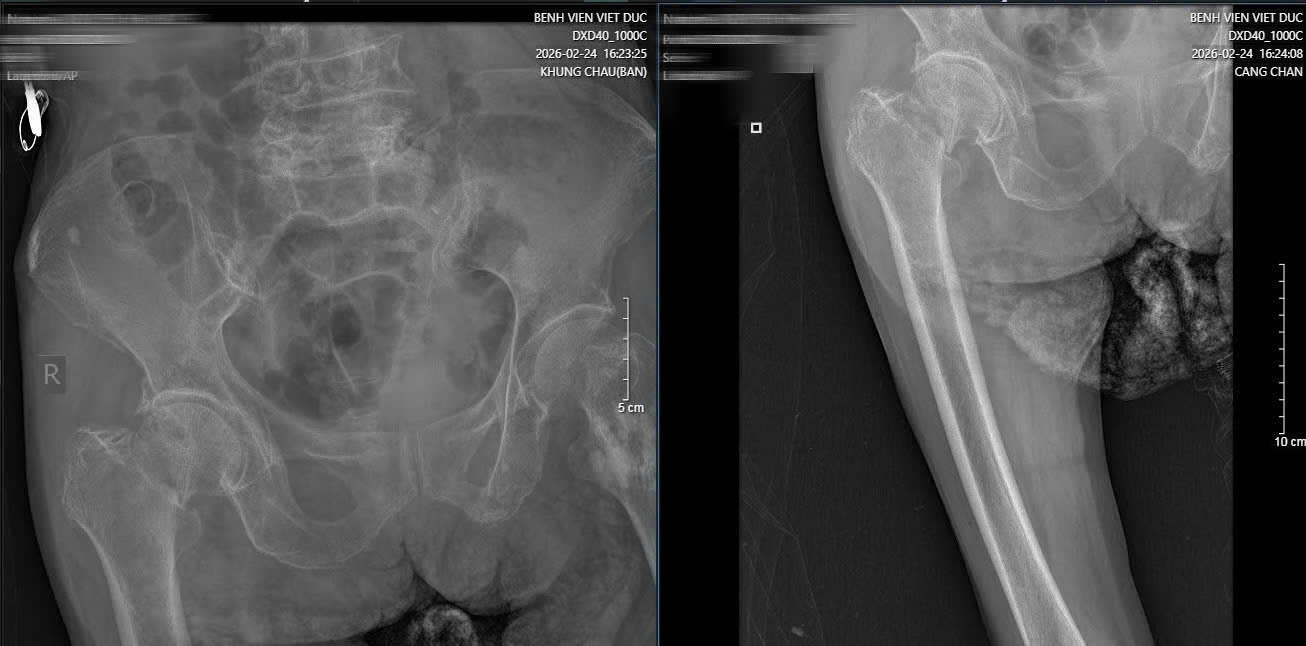

Hình ảnh phim X-quang cụ bà 89 tuổi nhập viện gãy cổ xương đùi phải và hình ảnh chụp CT ổ bụng và phát hiện khối u ruột non gây lồng ruột.

Sau một tuần, khi các chỉ số sức khỏe ổn định, cụ bà tiếp tục bước vào cuộc đại phẫu thứ hai. TS.BS Hoàng Ngọc Sơn đã trực tiếp phẫu thuật thay khớp háng cho cụ. Nhờ sự chuẩn bị kỹ lưỡng của đội ngũ y bác sĩ, ca mổ đã thành công tốt đẹp.